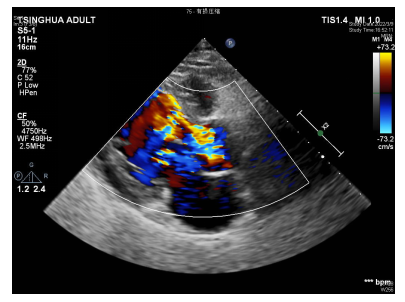

男性患者,58岁,因反复发热2周就诊。2周前,患者无明显诱因出现发热,为驰张热,最高体温39℃,无寒战、咳嗽咳痰、头晕头痛、腹痛腹泻、尿频尿痛等不适,无胸背痛、喘憋、呼吸困难、心悸、大汗等不适。就诊附近医院化验白细胞升高,口服头孢抗生素,体温降至正常后停药,2天后再次出现上述发热情况。再次就诊时检查胸部CT时发现胸主动脉增宽,未见明确肺部感染征象。进一步行主动脉CTA发现Stanford B型主动脉夹层(如图1)并收治入院。入院后超声心动图检查,提示主动脉瓣占位(赘生物不除外)、重度关闭不全(如图2-A,B,C);血培养发现星座链球菌,考虑感染性心内膜炎,瓣膜赘生物形成。

(图2-A,B)主动脉瓣可见赘生物,舒张期脱入左室流出道。

(图2-C)主动脉瓣大量返流

心脏超声:左室舒张末径63mm,左室收缩末径49mm,LVEF:54%。主动脉瓣三瓣叶,均毛糙,其上探及数个不规则条索样回声,长约13-26mm不等,随心动周期摆动,舒张期脱入左室流出道,致瓣膜闭合不全,主动脉瓣瓣大量返流;二尖瓣前叶瓣尖略增厚、回声增强,瓣叶开放尚可,关闭欠佳,二尖瓣少量返流;余瓣膜形态及结构未见异常。结论:1、主动脉瓣占位,赘生物可能性大,重度关闭不全;2、左心室增大,室间隔增厚;3、二尖瓣少量返流;4、左室整体收缩功能减低